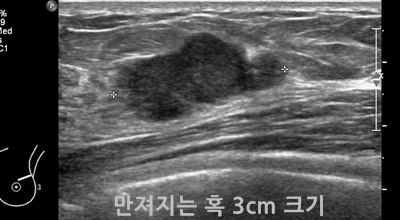

유방 밖으로 퍼진 악성 종양으로 생명을 위협할 수 있어요. 유방암은 보통 유방의 유관과 소엽에서 생기는데요 남성도 드물게 유방암에 걸릴 수 있어요. 유방암은 아직 명확한 원인이 알려지지 않았어요. 하지만 여러 가지 위험 요인을 추정할 수 있는데요 유전, 호르몬, 노화, 음주, 비만 등이 있답니다. 가장 흔한 증상은 유방에 발생하는 종괴입니다. 그리고 유두 분비, 유방통, 피부궤양, 함몰, 겨드랑이 종괴 등이 나타날 수 있어요. 증상들이 꼭 유방암을 나타내는 것은 아닐 수도 있으므로 정확한 검사가 필요하다고 해요.